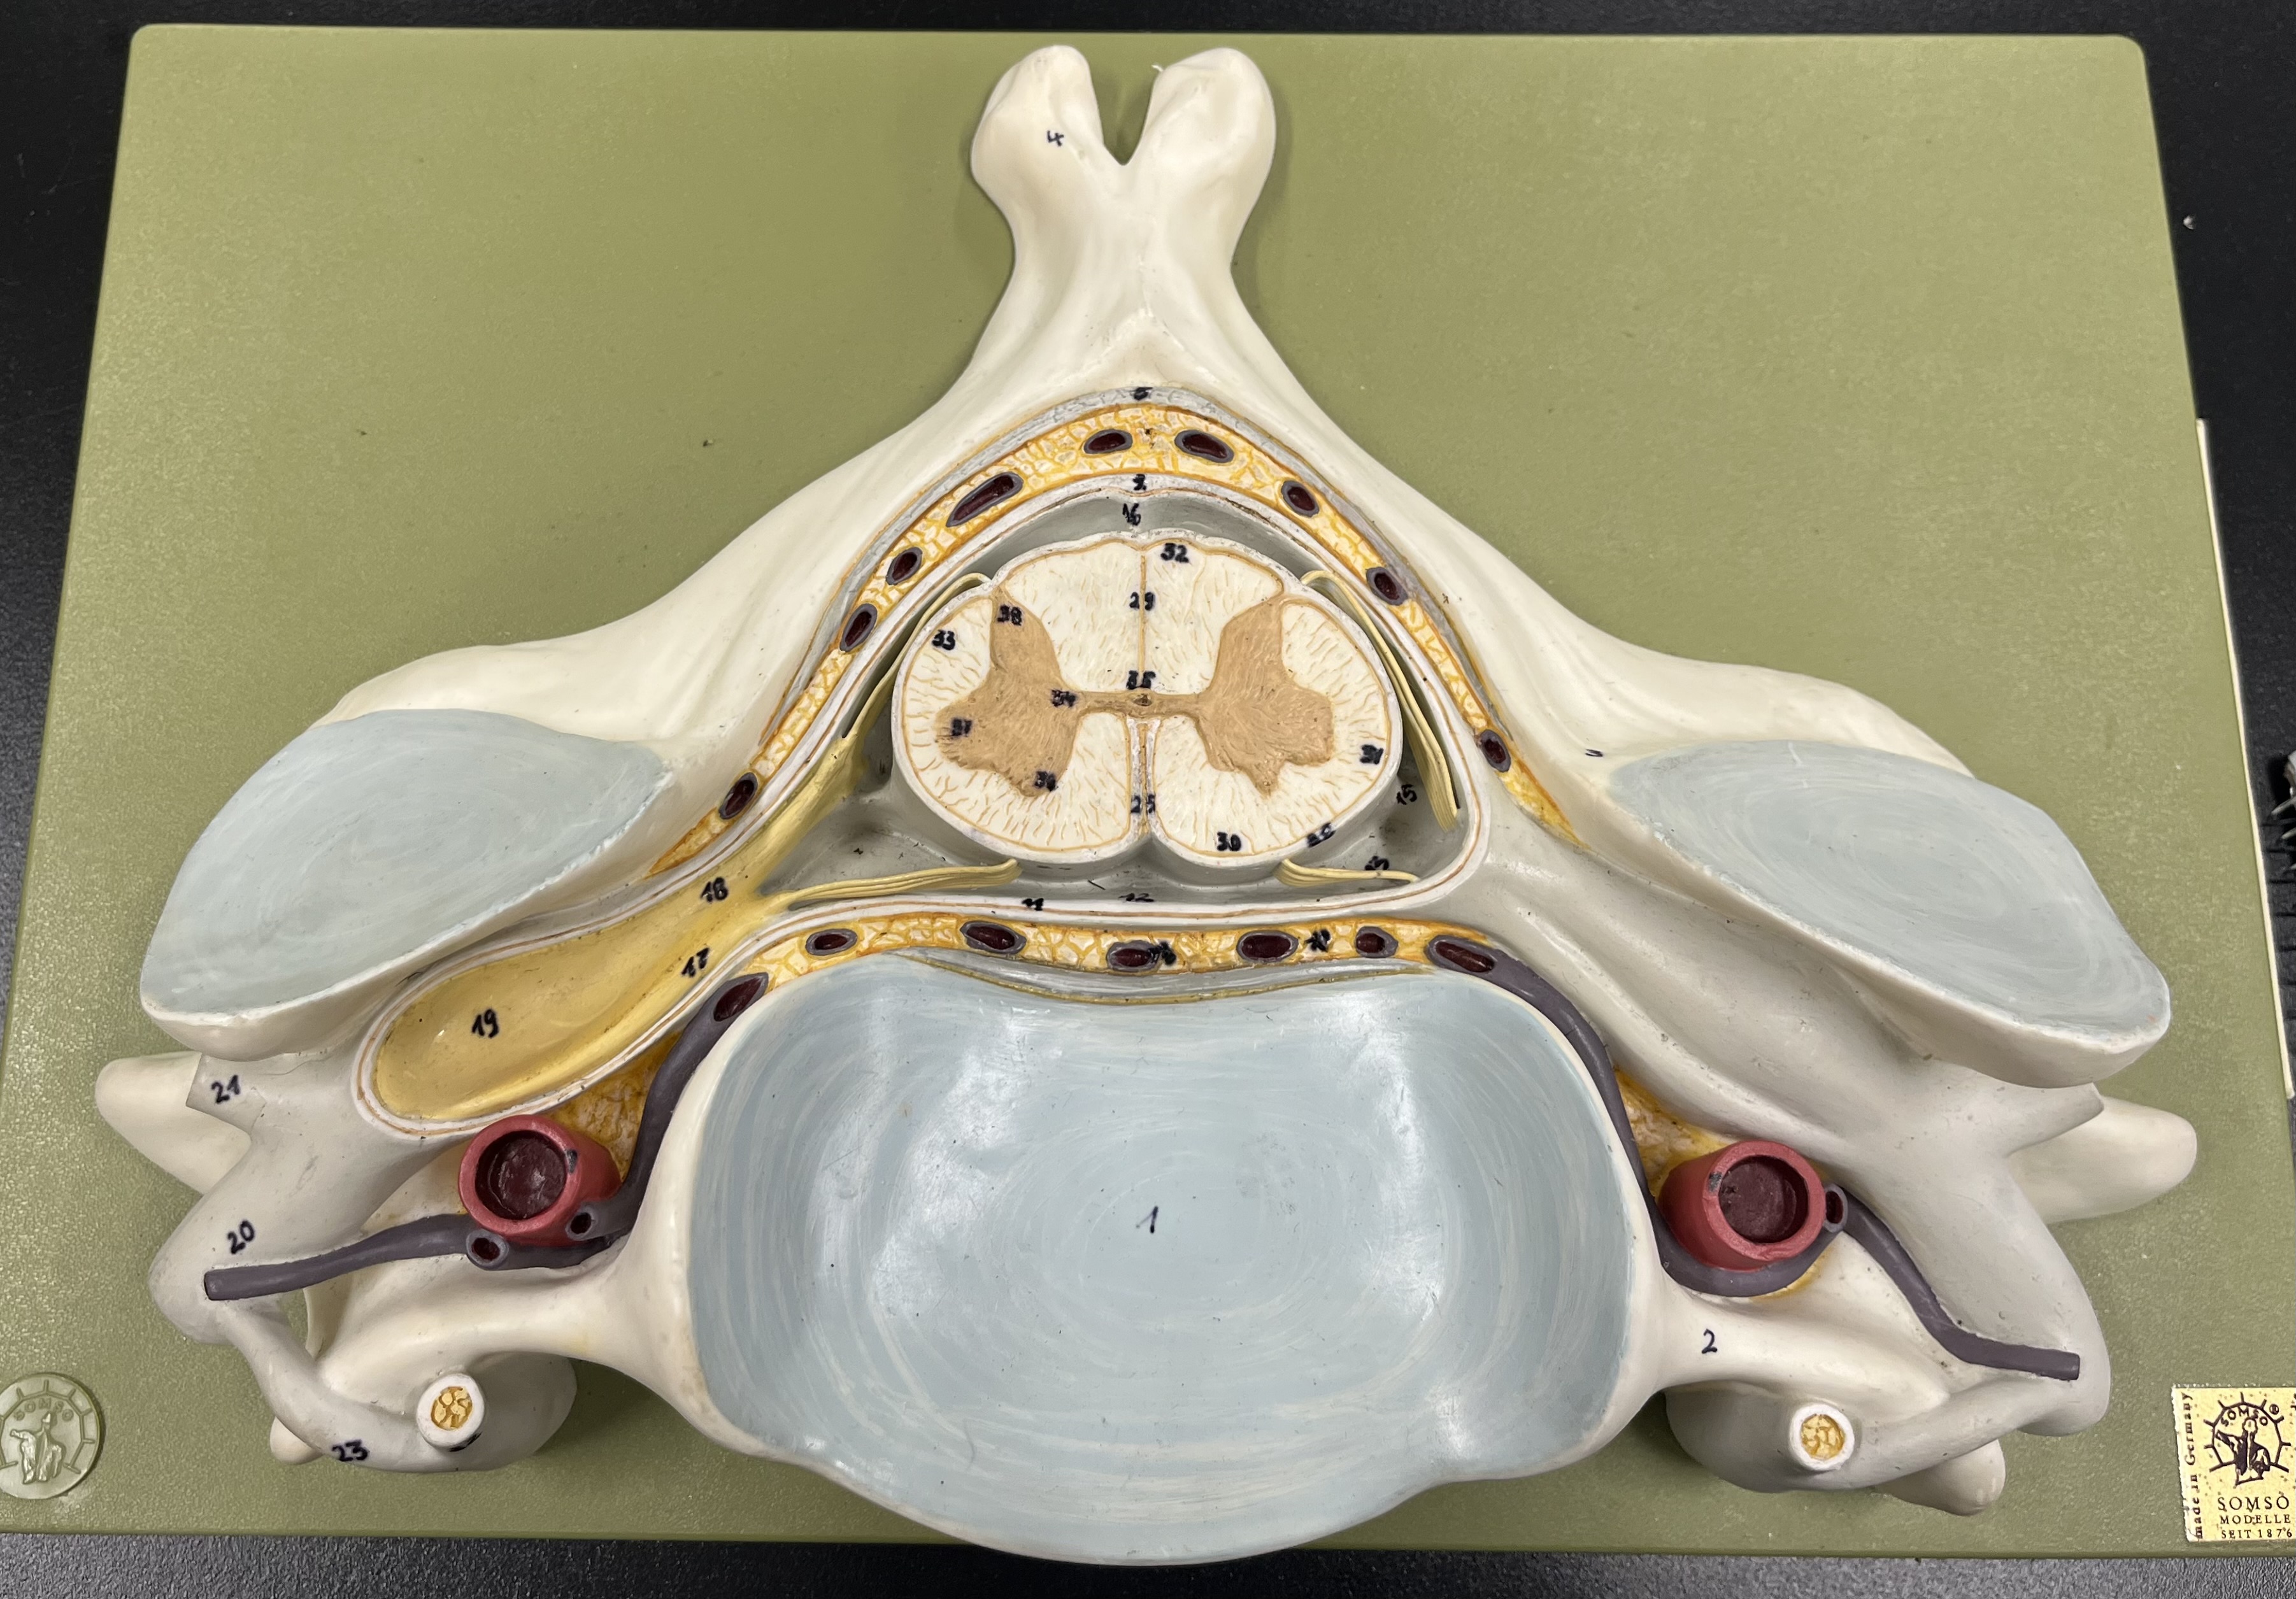

epidural space

dura mater

subdural space

arachnoid mater

subarachnoid space

pia mater

denticulate ligaments

What is the groove here?

anterior median fissure

posterior median sulcus

posterior (dorsal) horn

posterior (dorsal) horn; R—>L

anterior (ventral) horn

lateral horn (selected models)

gray commissure

central canal

anterior column

lateral column

posterior column

white commissure

posterior (dorsal) root ganglion

What is the bulb here?

posterior (dorsal) root ganglion

posterior (dorsal) root

posterior (dorsal) root

anterior (ventral) root

anterior (ventral) root

dorsal ramus

dorsal ramus

ventral ramus

ventral ramus

rami communicantes

rami communicantes

sympathetic chain ganglia

sympathetic chain ganglia